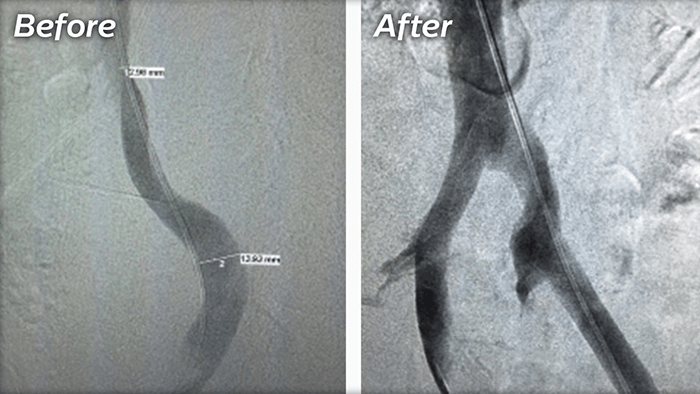

A minimally invasive treatment that uses lasers, radiofrequency, non-thermal ablation or mechanochemical ablation to shut down large varicose veins in the legs.